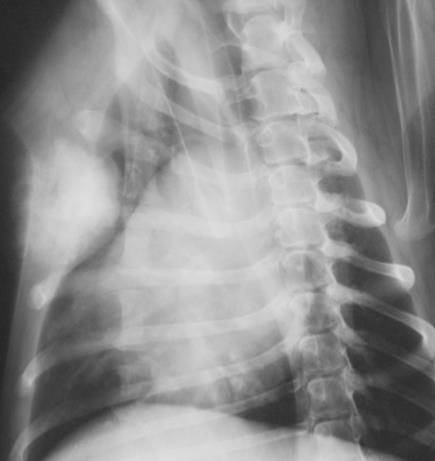

Discuss this radiograph?

Rib Tumour

May be lesions explaining clinical signs of the animals

Came in with a mass, owner noticed lump. Can see the mass.